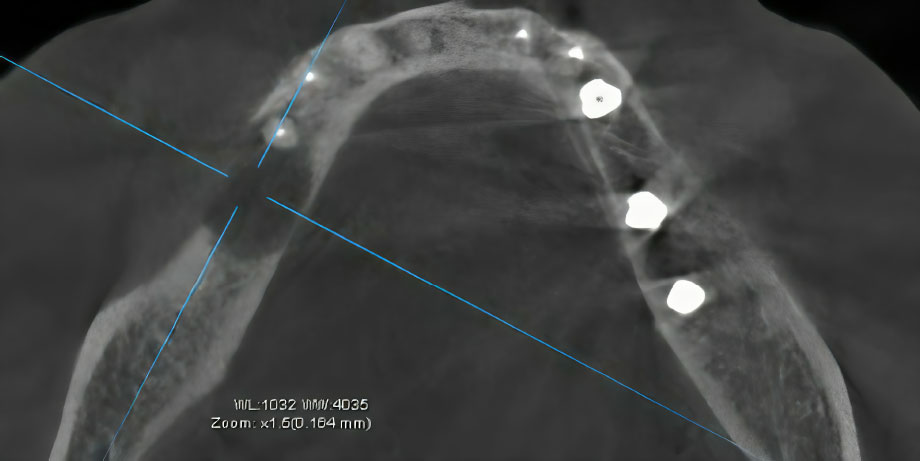

At a follow-up examination in April 2025, a mobile sequestrum was identified, which incorporated the dental implant at site #46. A subsequent CBCT scan confirmed the presence of a fully formed bone sequestrum (Fig. 3).

Sagittal CT projection demonstrating a fully formed sequestrum incorporating the dental implant at site #46.

The patient was monitored regularly. At a follow-up examination in April 2025, the condition had progressed. The implant was now mobile, and a mobile bony sequestrum incorporating the dental implant body was clinically evident. A subsequent CBCT scan confirmed the presence of a fully formed bone sequestrum (Fig. 3).